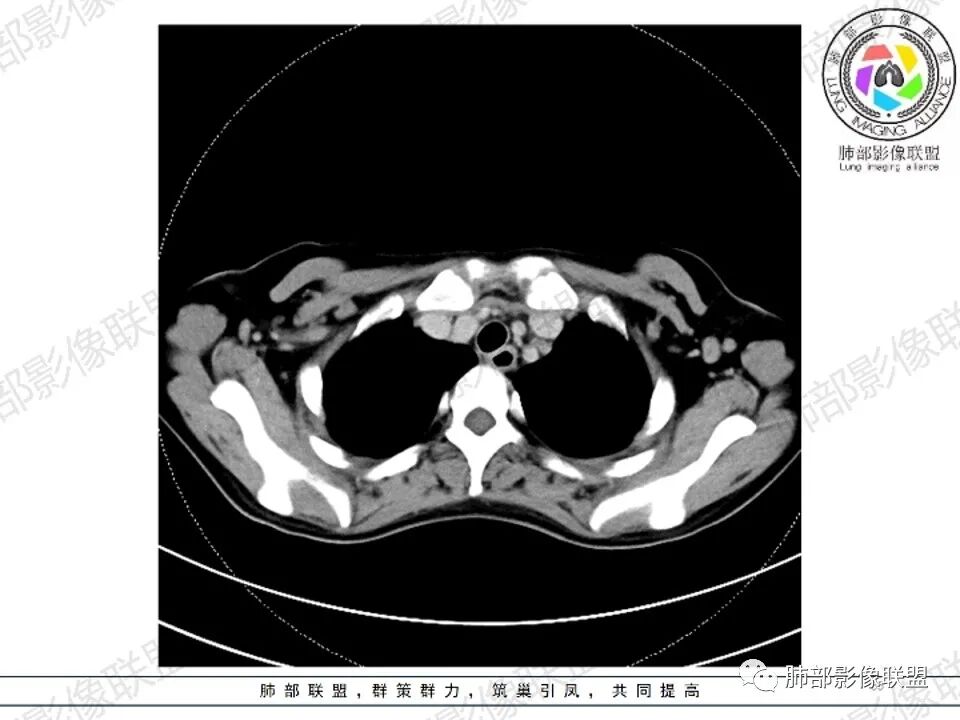

女,27,间断头晕、乏力3年,左眼视物模糊2月。贫血。胸部CT:前纵隔不规则肿块,多结节融合,边界不清,沿主动脉及肺动脉间隙生长,平扫密度欠均匀,增强扫描可见多发低密度坏死,纵隔血管供血穿行,腋窝多发大小不等淋巴结肿大。考虑恶性病变,胸腺癌?肉瘤?淋巴瘤?鉴别胸腺瘤、结节病等。

临床:年轻女性,慢性病程,多系统病变,头晕,贫血,视物模糊。

CT:定位纵膈病变,前中纵隔多发肿块,质软,塑形,密度不均匀,边界清楚。增强不均匀强化,坏死边界清楚,血管漂浮征。双侧腋下多组淋巴结肿大,明显异常强化。

2.影像显示前纵隔不规则块状影,依势贴附心脏大血管旁,密度不均,边界不甚清楚,有结节融合感。

3.病灶轻度不均匀强化,可见血管穿行,散在液性低密度区。

4.双侧腋窝区见增大淋巴结,边界清楚。

1.年轻女性,前纵隔不规则块状影,密度不均,边界不甚清楚,有结节融合感,轻度不均匀强化,可见血管穿行,最常见最符合的无疑是淋巴瘤!